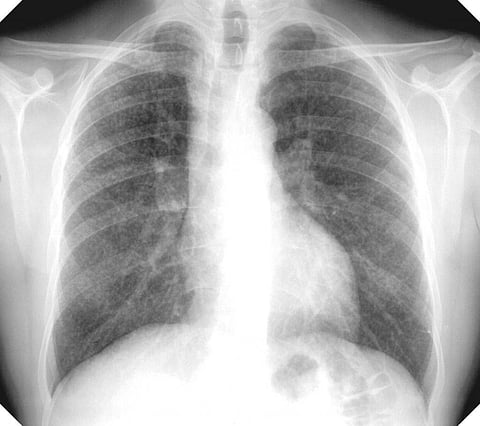

सिलिकोसिस एक ऐसी बीमारी है जो विभिन्न व्यावसायिक रूपों देखने को मिलती है। आयुध कारखानों में सिलकोसिस का दायरा 3.5 प्रतिशत है तो स्लेट-पेंसिल उद्योग में 54.6 प्रतिशत कामगार इस जानलेवा बीमारी से ग्रस्त पाए जाते हैं। बीमारी के विस्तार में इस तरह की विविधता के लिए कई कारक जिम्मेदार हैं। इनमें अलग-अलग वातावरण में सिलिका कणों का घनत्व, कार्य की जरूरतों और सिलिका कणों से संपर्क की अवधि मुख्य रूप से शामिल है। ओडिशा, गुजरात, राजस्थान, पांडिचेरी, उत्तर प्रदेश, हरियाणा, झारखंड और पश्चिम बंगाल के निर्माण एवं खनन गतिविधियों से जुड़े कामगार इस बीमारी से सबसे अधिक प्रभावित हैं।

सिलिकोसिस एक लाइलाज बीमारी है जो अंततः मरीज को निष्क्रिय बनाकर छोड़ देती है। कोई स्पष्ट उपचार नहीं होने के कारण सिलिकोसिस से बचाव का एकमात्र उपाय कामगारों को सिलिका युक्त धूल कणों के संपर्क में आने से रोकना है। शोधकर्ताओं का कहना है कि इस उपकरण के उपयोग से विभिन्न व्यावसायिक गतिविधियों से जुड़े स्वस्थ कामगारों का श्रम बल तैयार करने में मदद मिल सकती है। (इंडिया साइंस वायर)